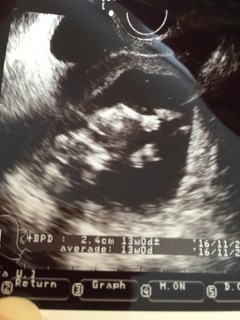

5本の指!左のお手てがくっきり。初めて経腹エコーしたけど、ボヤけてて写りが悪く…今まで通り下からエコーでちゃんと写りました!次回は、経腹エコーできるかな?楽しみ!!ベビーちゃんの頭は2.4cm。アベレージは13wの大きさでした!

初の経腹エコー。じっとしてなくて、先生を困らせてました(ーー;)頸管が3センチ未満で、切迫流産・早産の危険があるとの事で自宅で安静中です(>_<) 次の診察は、また2週間後。 元気に生まれてくれる事を祈るばかりです(´-_-。`)